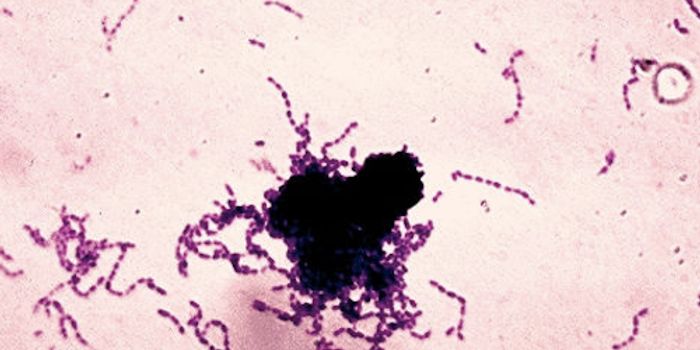

SEP 13, 2015MicrobiologySalmonella enterica are a group of rod shaped bacteria that are most commonly associated with foodborne illness in human ...

JUN 25, 2015Health & MedicineSalmonella enterica is the number one cause of bacterial foodborne illness worldwide. Infections can be transmitted by a ...